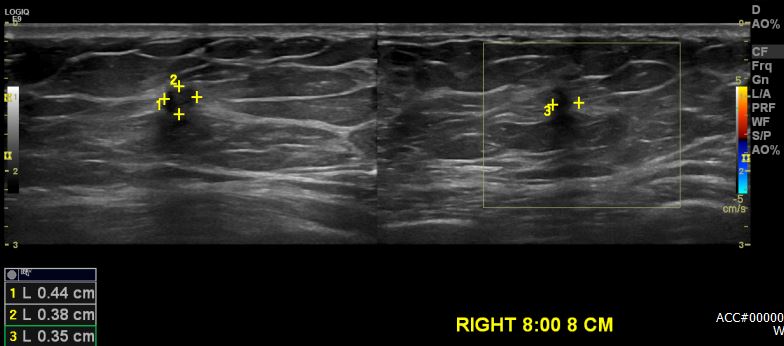

건강검진상 이상소견으로 내원하신 50대 여성분으로 본원 초음파상 우측유방

8시 방향에서 8cm 떨어진 거리의 의심스러운 멍울 조직검사 시행하여 우측 침윤성

유관암 진단 되었습니다.